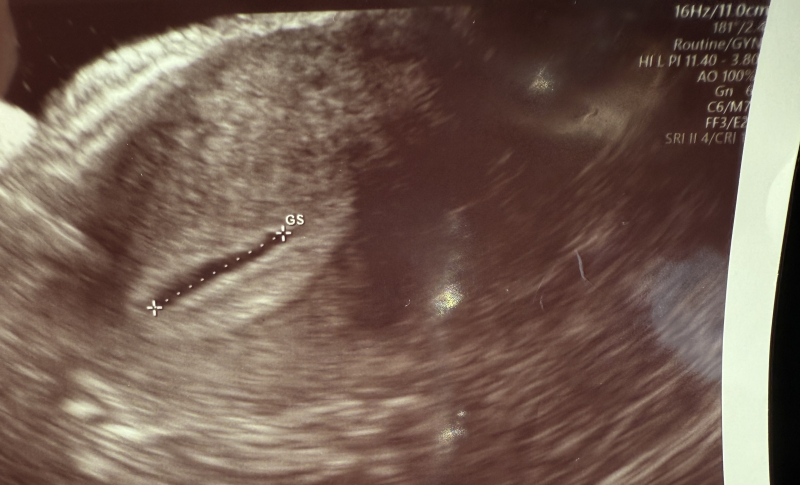

受診した際エコーをしてもらったのですが、胎嚢のみの確認で、とーーっても細長い胎嚢しか確認出来ず不安です。

上2人は丸い胎嚢だった気がします、、

先生には膀胱張ってるよね?圧迫されてこの形になってると思う、出血したら電話してきてね、と言われました。

調べると細長い胎嚢は流産の確率が上がる、や、子宮に吸収される時にこの形になると書かれていたり不安です。

確かに尿検査があると思い、尿は溜まってたのですがそれで胎嚢が圧迫されることはあるのでしょうか?